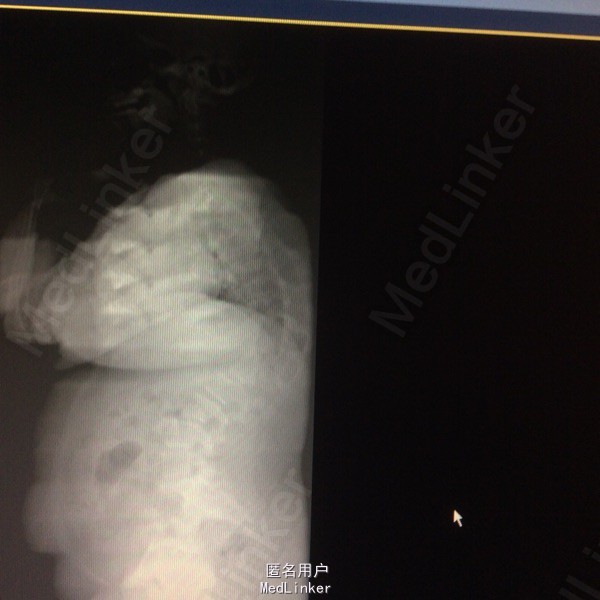

站立位腰背部疼痛5个月 五月前检查发现腰背部畸形伴疼痛,未行特殊治疗。

患者呈向心性肥胖,眼角略上斜,下颌小,上下牙间距大,闭齿音发音不清,性早熟,外阴幼稚,大小阴唇发育不良,手脚小胖,指端纤细,余查体无明显异常。 辅助检查:胸9-10胸12-腰1椎体融合、胸11呈半椎体,椎管内脊髓未见明显信号异常.

胸椎半椎体畸形 左侧第10肋骨缺如 隐形骶椎裂 双下肢膝外翻 双下肢肌挛缩症 脊柱畸形术,胸5、6、8、9腰1-2-3双侧椎弓根螺钉,去除胸11-12后方椎板,胸12半椎体及上下间隙间盘去除,椎间隙植骨。